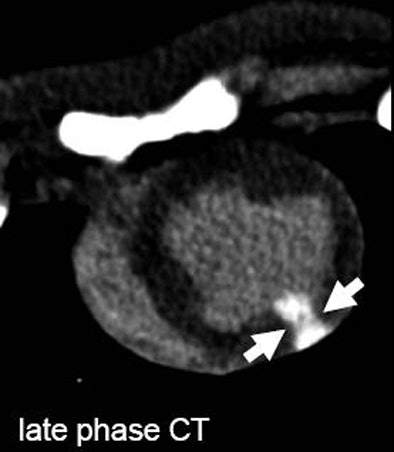

| The arrows on unenhanced CT show a hypodense area corresponding to edema as it can be seen on T2-weighetd MRI. The arrows on late-phase CT and MR correspond to infarction. The area of edema is larger than the area of infarction as expected based on previous MRI studies for the imaging of myocardial edema. All images courtesy of Dr. Andreas Mahnken. |

According to the results, mean MI sizes on unenhanced, arterial, and late-phase DSCT were 27.2 ± 8.5%, 20.1 ± 6.9%, and 23.1 ± 8.2%, respectively. The corresponding values on T2-weighted and delayed enhanced CMR were 28.5 ± 7.8% and 22.2 ± 7.7%. Size of MI on TTC staining was 22.6 ± 7.8%.

The best agreement was found in the comparison between late-phase CT (pc = 0.9356) and delayed enhanced CMR (pc = 0.9248) with TTC staining. The group also found substantial agreement between unenhanced DSCT and the T2-weighted CMR images (pc = 0.8629).